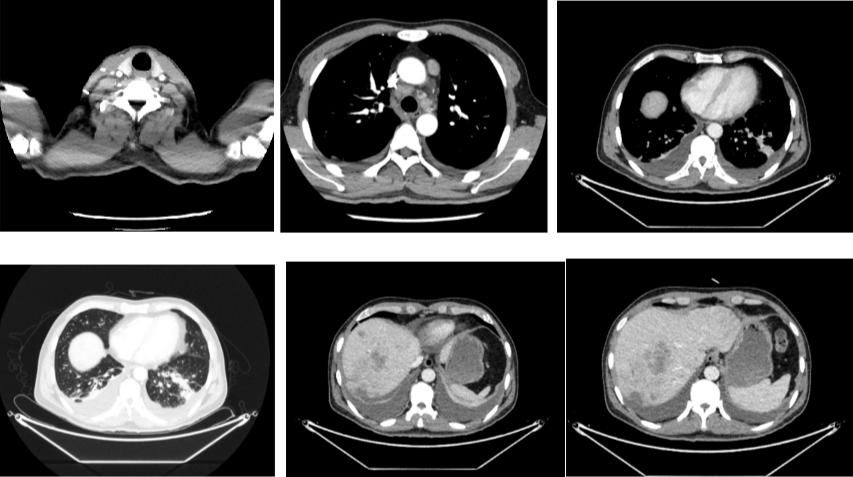

2020年4月复查:持续PR

肿瘤标志物:均正常

肝功能正常。

增强CT示:肝硬化

肝异常强化灶

考虑酒精性肝硬化可能性大,未基线使用替吉奥维持治疗。

胃癌并肝转移化疗后,肝内转移灶大致同期;

慢性肝病,脾大、门脉高压(食管下段-胃底静脉曲张);

右肺中叶外侧段、左肺上叶下舌段及右肺下叶后基底段慢性炎症;

右肺上叶前段实性微小结节,炎性结节?建议定期复查;

纵隔淋巴结转移瘤,复查大致同前。